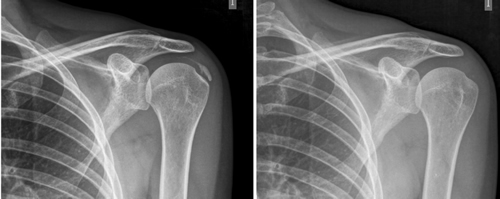

El número promedio de sesiones en nuestra serie fue de 20. El criterio para continuar o suspender el tratamiento fue la evolución radiológica y clínica (Figuras 4 y 5). Las intervenciones se realizaron hasta un máximo de 40 sesiones. Perrón trató a sus pacientes por 9 sesiones (3 sesiones semanales por 3 semanas) (14). Leduc trató con 10 sesiones (3 por semana las dos primeras semanas; y luego una semanal por 4 semanas) (15). Rioja-Toro trató a sus pacientes por 40 sesiones (5 veces por semana) y los evaluó a las 20 y a las 40 sesiones (3). Chico-Álvarez trató a sus pacientes entre 15 y 30 sesiones dependiendo de la evolución radiológica (5 veces por semana) (1).

Fig. 4. Paciente mujer de 47 años con tendinitis calcificante de supraespinoso derecho, de tipo formativa, quien tras 30 sesiones de iontoforesis disminuyó el dolor medido por EVA de 6/10 a 3/10 y la calcificación de 38 mm a 8 mm (valoraciones al inicio, a las 10, a las 20 y a las 30 sesiones, respectivamente).

Fig. 5. Paciente mujer de 44 años, con tendinitis calcificante de supraespinoso izquierdo, de tipo resortivo, quien tras 20 sesiones de iontoforesis disminuyó el dolor medido por EVA de 10/10 a 4/10, y la calcificación de 22 mm a 0 mm (desaparición completa).